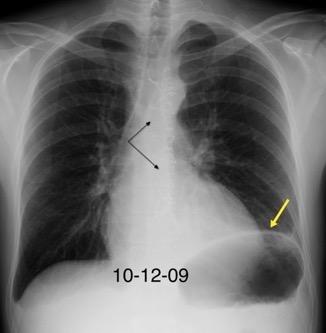

Tromboembolismo pulmonar Diafragma elevado 20%

Atelectasia crónica de LLI en paciente con enfermedad neuromuscular.